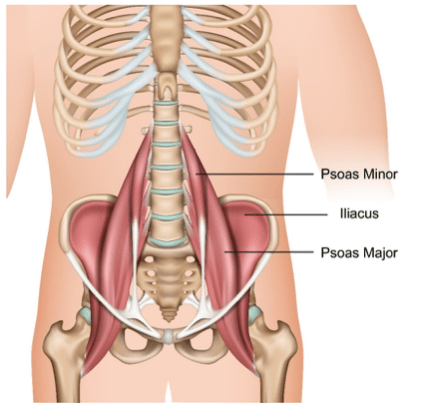

After a total hip replacement some Patients (like me) can be susceptible to iliopsoas tendinopathy and/or bursitis after a total hip replacement. This often occurs due to friction of the bursa and tendon over the new metalwork. Patients experiencing these symptoms can respond very well to injection therapy. So the plan is to have the psoas injected and see if this will give me a ‘pain free window’ in which to increase physio and stretches. If not I might ask about an ilopsoas tendon release surgery.

No need to change into a gown,nor have the marker pen arrow drawn on. Just pulled leggings down, lie down and discuss issues I’ve been having. Then had an ultrasound to locate the tendon and assess the inflammation. They stated it didn’t look severe, but also it’s very deep so could be hidden too. Also didn’t appear to be trapped by acetabular cup, so that’s good news.